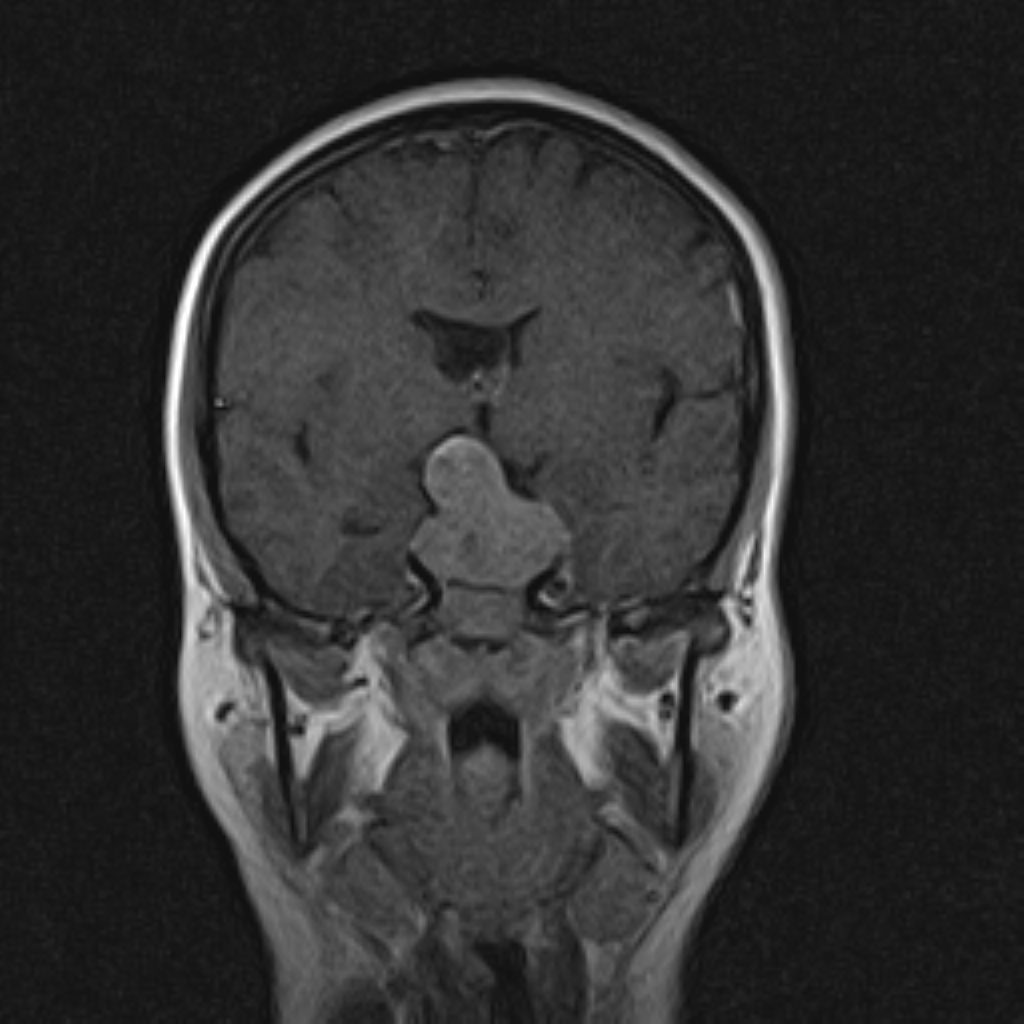

HYPOPHYSIS MRI

(with and without contrast)

Technique: Axial , coronal T1 , Axial , coronal , sagittal T2 , Axial, coronal T1 post Gd & 64 dynamic thin coronal slices.

REPORT :

The infundibulum is centered and of normal size .

The cavernous sinus and imaged portions of the internal carotid artery and carotid siphon are unremarkable .

The sphenoid sinus is clear and pneumatized .

– A large extra axial – iso signal mass lesion ( 20 x 36 x 48 mm ) in pituitary fossa with extention to supra sella cistern & mass effect in chiasma optic with partial encasement of right & left ICA with pituitary expansion & with post contrast homogeneous enhancement suggestive for pituitary macro adenoma ( snow man disease )